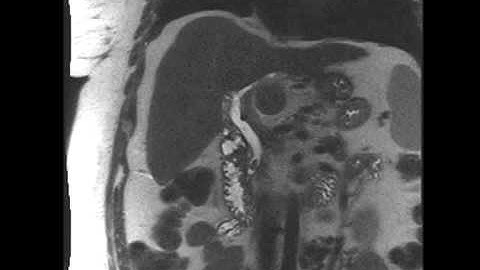

Proximal Cholangiocarcinoma